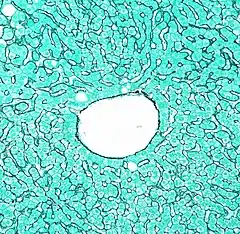

Las venas centrales intralobulillares o centrolobulillares, (TA: venae centrales hepatis) son las venas microscópicas de la parte central de los lobulillos hepáticos, y que drenan en las venas hepáticas.[1]

Cada vena centrolobulillar, se encuentra en el centro de la estructura celular tridimensional, de forma prismática hexagonal llamada lobulillo.

La vena central de 150-200 μm de diámetro, está conformada por células endoteliales. Es sostenida por: una red laxa de delgadas fibras reticulares, por los cuerpos de hepatocitos adyacentes y por los sinusoides que desembocan en ella.[2][3]